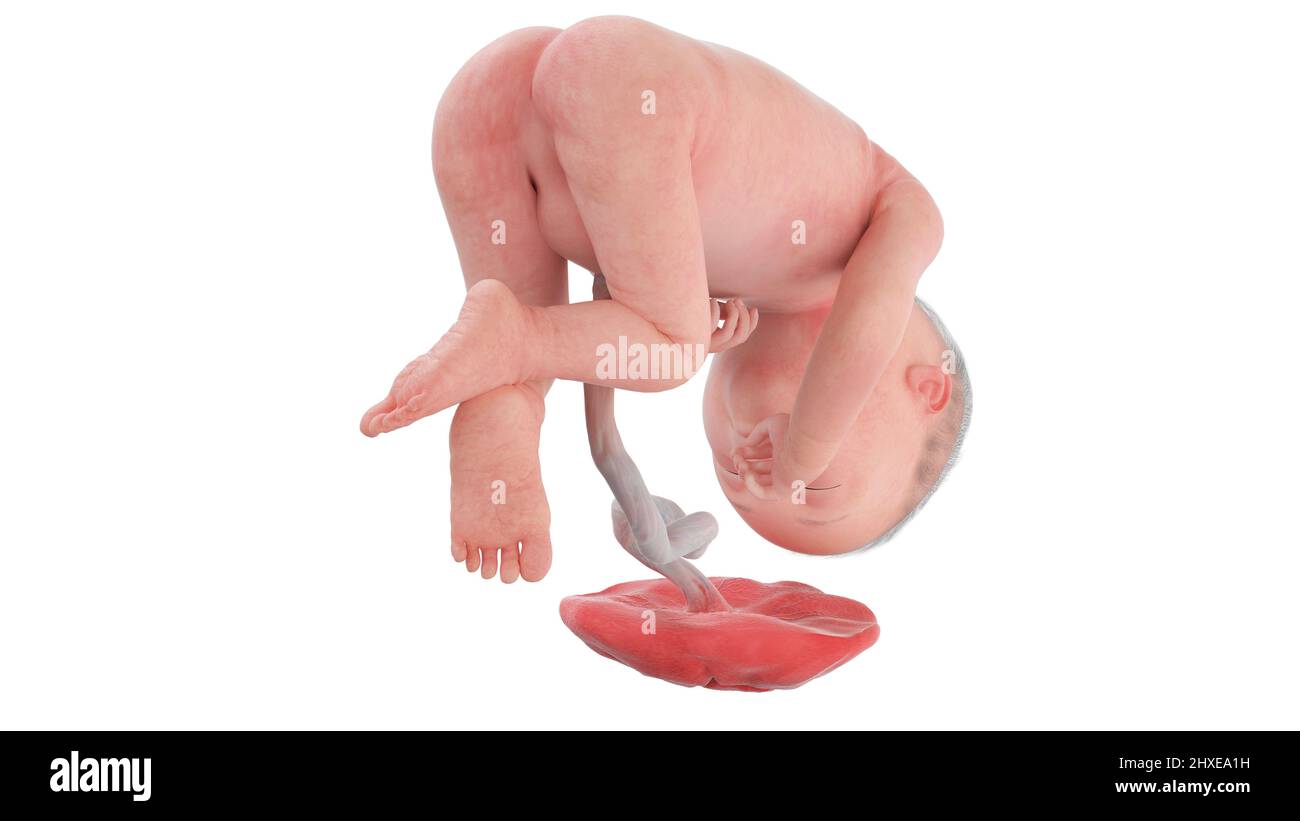

Feto umano alla settimana 27, illustrazione Foto Stockhttps://www.alamy.it/image-license-details/?v=1https://www.alamy.it/feto-umano-alla-settimana-27-illustrazione-image463765837.html

Feto umano alla settimana 27, illustrazione Foto Stockhttps://www.alamy.it/image-license-details/?v=1https://www.alamy.it/feto-umano-alla-settimana-27-illustrazione-image463765837.htmlRF2HXEA1H–Feto umano alla settimana 27, illustrazione